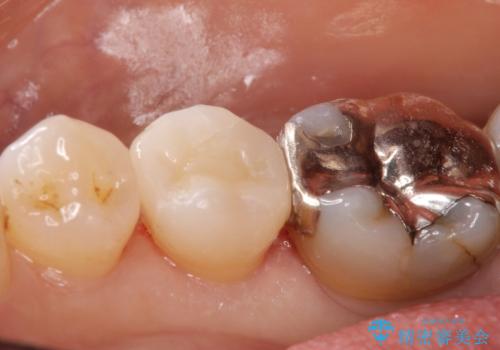

白い詰め物が入り大変満足して頂けました。

現在、奥歯の銀歯も治療を検討中です。